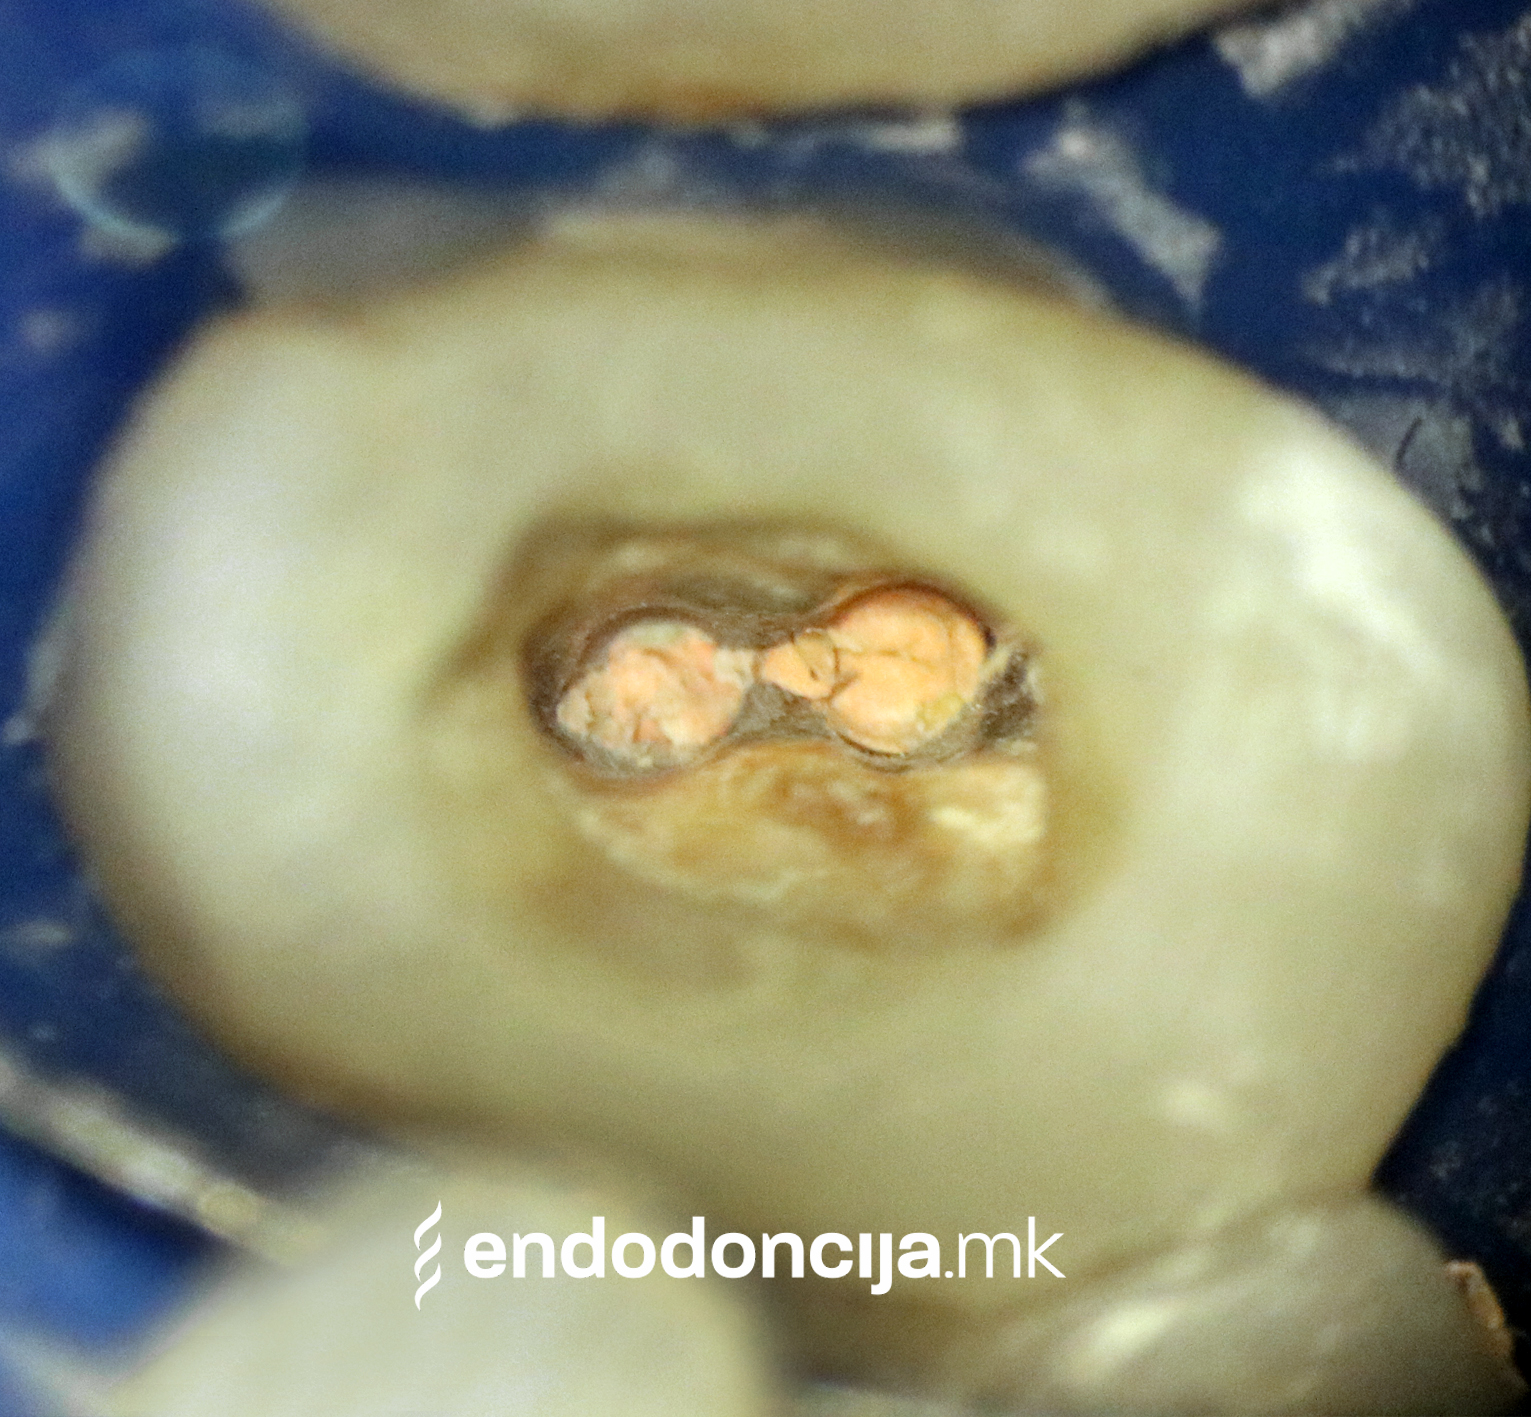

На специјализираниот оддел за ендодонција, нашите пациенти ги лекуваме на највисоко професионално и дијагностичко ниво. Опремени сме со најсовремени хируршки микроскопи, кои поддржуваат детален приказ и подготовка на коренот и нудат комплетно ново ниво на прецизност. Најновата ендодонтска опрема, инструментите и материјалите за полнење се во секојдневна употреба. На овој начин третманот станува пократок, дури и во комплицирани случаи, и се избегнува губење на забите.

Она што е импресивно е прецизноста на микроскопските третмани. Дури и кога каналите се потешко достапни, може да се лоцираат и исчистат така што релапсите се со помала веројатност. Спротивно на тоа, скриените канали често остануваат неоткриени во конвенционалниот третман на коренскиот канал и затоа не можат да се чистат. Бактериите можат да се размножуваат таму без пречки и да предизвикаат воспаленија. Ова често останува незабележано со години додека не се појави забоболка, а со тоа и компликации.

Употребата на микроскоп исто така овозможува детектирање пукнатини или фрактури што може да предизвикаат болка или воспаление.